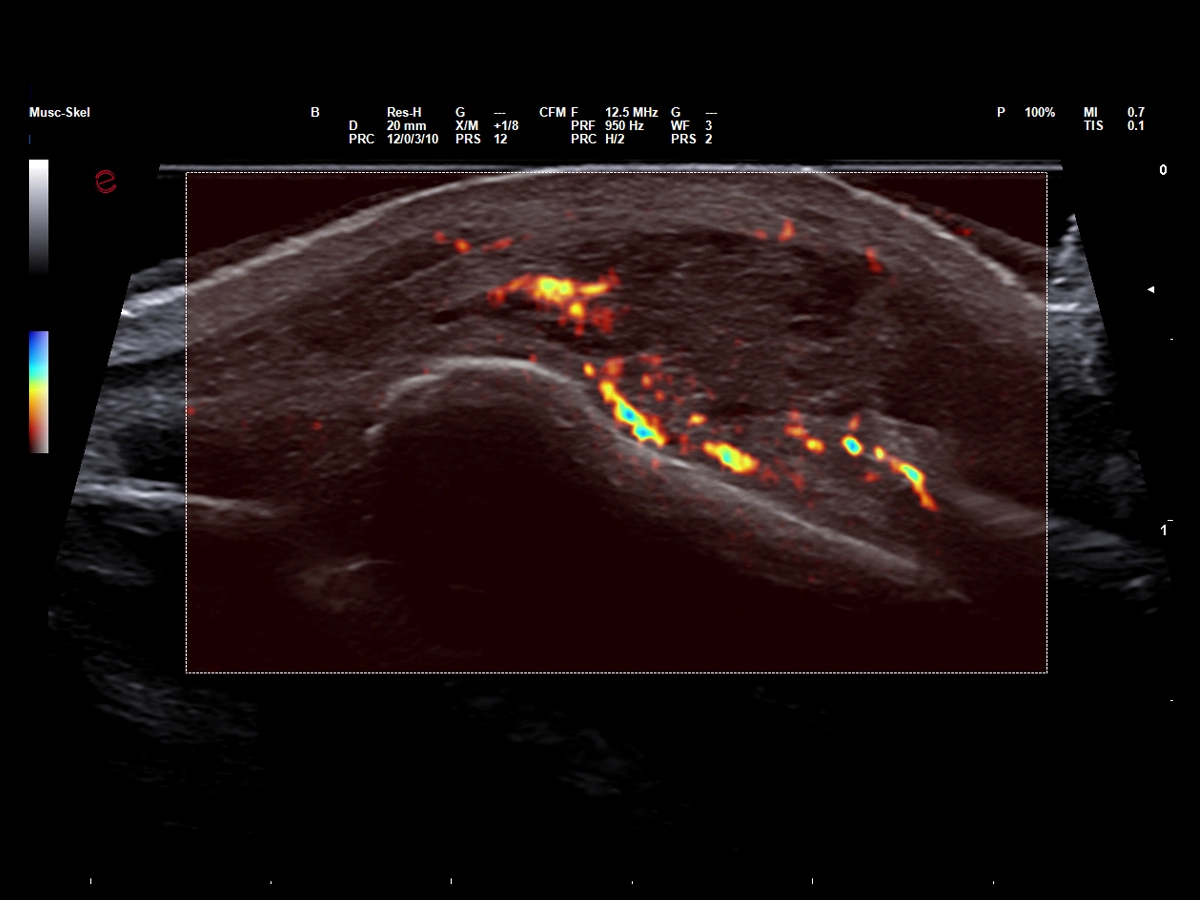

Microvascular insights in sports medicine

In sports medicine, Power Doppler allows for accurate evaluation of inflammation and monitoring of healing, particularly in soft tissue and overuse injuries. Esaote’s highly sensitive Power Doppler technology has been designed to optimize visualization of lowflow signals in small, superficial vessels, which are typical of early or low-grade inflammatory processes, thereby supporting accurate diagnoses and tailored follow-up. With the addition of microV technology, Esaote is pushing the boundaries of microvascular imaging, enabling early detection and detailed characterization of musculoskeletal injuries, which is vital for their effective management and for developing faster return-to-play strategies.